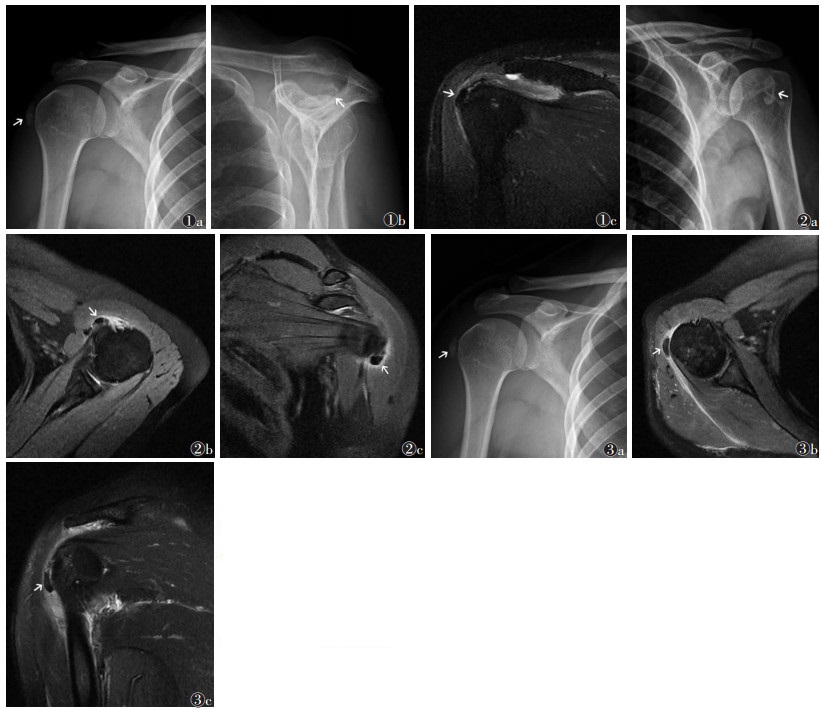

2 结果37例中,发生于左肩13例,右肩24例。钙盐沉积32例单发,5例多发。MRI上钙盐沉积肌腱部位见表 1,不同肌腱部位钙盐沉积最大径比较差异无统计学意义(P>0.05)。91.9%(34/37)位于肌腱止点区,8.1%(3/37)位于止点区之外;94.6%(35/37)位于肌腱浅层滑囊面,8.1%(3/37)位于肌腱深层(图 1~3)。

| 图 1 女,61岁,右肩袖冈上肌及冈下肌肌腱钙化性肌腱炎 图 1a,图 1c 斜冠状位FSE脂肪抑制T2WI可见右冈上下肌及冈下肌肌腱止点区浅层滑囊面结节状低信号 图 2 女,64岁,左肩袖肩胛下肌肌腱钙化性肌腱炎 图 2a X线肩关节正位可见左肱骨上端近小结节处钙化灶 图 2b,图 3 女,43岁,右肩袖小圆肌肌腱钙化性肌腱炎 图 3a X线肩关节正位可见右小圆肌肌腱走行区肱骨头外侧肱骨大结节处钙化灶 图 3b,3c 轴位FSE脂肪抑制PDWI和斜冠状位T2WI可见右小圆肌肌腱浅层滑囊面结节状低信号 |

X线上冈上肌和(或)冈下肌肌腱部位的钙盐沉积均位于肩峰下至肱骨大结节间隙相应肌腱走行区,肩关节正位片均可显示,侧位由于各骨间相互重叠显示不清,冈上肌出口位钙盐沉积部分与肱骨头重叠;肩胛下肌肌腱钙化性肌腱炎,X线肩关节正侧位显示5例位于肱骨上端近小结节处;小圆肌肌腱部位的钙盐沉积位于小圆肌肌腱走行区肱骨头外侧近肱骨大结节处。

T2WI和PDWI抑脂序列83.8%(31/37)呈低信号,10.8%(4/37)呈等信号,5.4%(2/37)呈混杂信号;T1WI均呈低信号;周围软组织均有水肿信号。75.7%(28/37)合并肩峰-三角肌下滑囊积液,48.6%(18/37)合并关节腔积液,43.2%(16/37)合并冈上肌肌腱变性,24.3%(9/37)合并肱二头肌长头肌腱腱鞘积液,18.9%(7/37)合并喙突下滑囊积液,10.8%(4/37)合并冈上肌肌腱撕裂。X线片示91.9%(34/37)显示钙化灶,8.1%(3/37)无钙化灶。